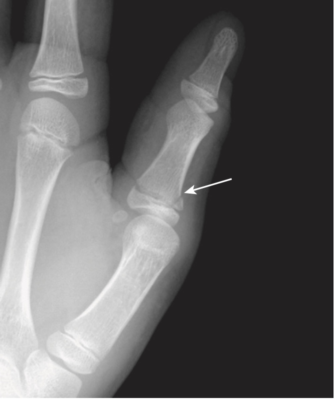

- Gãy xương của võ sĩ quyền anh (Boxer’s fracture): gãy cổ của xương bàn đốt ngón tay thứ 5 (ngón út) với di lệch gập góc về lòng bàn tay của đầu xa. Đôi khi cũng bị thêm xương bàn đốt ngón thứ 4. Gãy xương này thường do đấm tay vào người hoặc vào tường (Hình 13). Dù tên gọi võ sĩ quyền anh, những võ sĩ chuyên nghiệp thường không bị loại gãy này (lực đấm đúng thường tác động lên các xương đốt bàn ngón 2 và ngón 3 và xương quay).